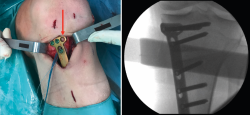

Posteriormente, bajo control radioscópico, se realiza la osteotomía apoyando la sierra por debajo de la aguja guía, llegando hasta 1 cm de la cortical lateral. Se introducen los escoplos para abrir la osteotomía (Figura 4). El primer escoplo, el más ancho, se introduce primero para comprobar el corte completo de la cortical posterior. Seguidamente, se coloca el medidor del ángulo de apertura (Figura 5A) y, a continuación, se introduce el distractor en la parte posterior de la osteotomía, evitando así un aumento de la PTP (Figura 5B). En este momento, se puede introducir en la apertura de la osteotomía el aloinjerto o sustituto óseo. Los autores utilizan aloinjerto óseo cuando la apertura es mayor de 10°. Antes de colocar y fijar la placa de osteotomía, se realiza el túnel tibial utilizando las herramientas artroscópicas clásicas (Figuras 6A y 6B). Al realizar una osteotomía biplanar, el corte es suficientemente distal como para permitir brocar el túnel tibial de la RLCA sin dificultades.

Figura 4. Colocación de escoplos de forma progresiva para realizar la apertura (una vez realizados los cortes con la sierra).

Una vez hecho el túnel tibial, se introduce la plastia y se fija a nivel femoral y tibial (Figura 7). Si se utiliza una plastia de isquiotibiales, los autores recomiendan una fijación femoral cortical de suspensión regulable, dejando unos milímetros para el ajuste final después de la colocación de la placa de osteotomía. Una vez fijada la plastia, se procede a la colocación de la placa de osteotomía TomoFix® (Synthes, Oberdorf, Switzerland) para la tibia proximal medial (Figura 8). En la mayoría de los casos el tornillo más anterior coincide con el túnel tibial de RLCA, motivo por cual no se coloca (Figura 9).

Figura 6. A: colocación de la aguja guía para realizar el túnel tibial; B: brocado del túnel tibial. Se observa el espacio metafisario suficiente para realizar el túnel tibial, sin interferencias con la osteotomía.

Figura 7. Introducción de la plastia a través del túnel tibial, manteniendo el distractor en posición.

Figura 8. Colocación de la placa TomoFix® para la tibia proximal medial una vez fijada la plastia de ligamento cruzado anterior a nivel femoral y tibial.

Figura 9. Fijación de la placa con tornillos. Se señala con la flecha la ausencia del tornillo más anterior, dada su coincidencia con el túnel tibial.